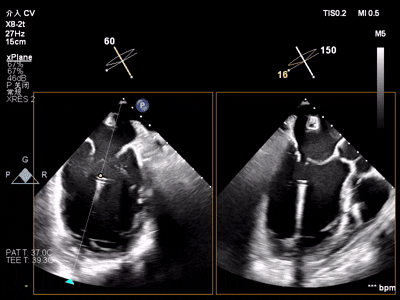

【术中操作(含关键步骤超声)】

鉴于患者术前心功能差、多支架植入的特殊情况,手术全程需兼顾“精准操作”与“保护心功能”双重要求:在全麻与经食道超声的协同引导下,团队先突破心功能受损导致的术野稳定性难题,稳步经心尖建立手术轨道与输送鞘;随后聚焦二尖瓣2偏3区精准置入一枚Ⅱf型夹合器,成功攻占这一解剖位置深、毗邻结构敏感、容错率极低而操作难度陡增的区域。

手术中,主刀术者常青教授稳定发挥,经过严谨的策略思索,挑战超精细微调整与瞬间捕获夹合,逐步逆转反流症状。从显著改善到最终完全消除,全程仅约25min的导管操作时长。在高危病例的严苛挑战下,凸显了团队操作的娴熟度与安全性。